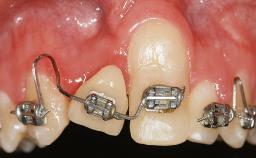

Soft-Tissue Volume Augmentation Using a Connective-Tissue Graft Harvested from the Maxillary Tuberosity

In 1983, a 51-year-old non-smoking patient was referred for the treatment of moderate chronic periodontitis. At the initial examination, 47% of sites exhibited probing depths of 4 to 6 mm. Periodontal therapy consisted of initial periodontal treatment including oral-hygiene instructions and supra- and subgingival debridement, followed by periodontal surgery to eliminate residual pockets.